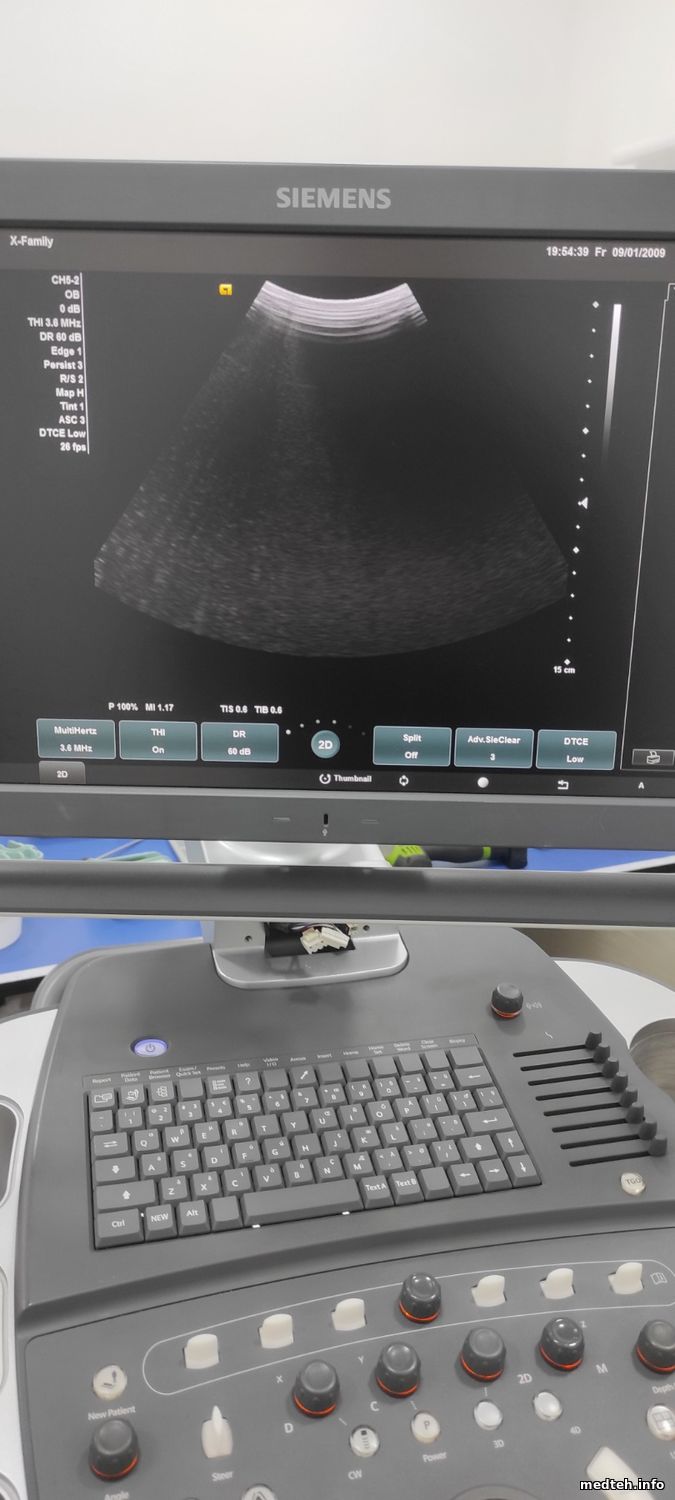

Имеется на обслуживании Acuson X600 корпорации Siemens, со слов врача система отключался при работе с линейным датчиком в режиме цветного доплера и не реагировал при нажатии на кнопку питания.

После технического обслуживания, то бишь чистка всей системы от пыли и т.п., система загружается нормально, не выключается при запуске цветного доплера.

Но во время исследованиях имеются АРТЕФАКТЫ.

Возможно кто-то сталкивался с подобной ситуацией и подскажет в каком направлении двигаться.

Фото прилагаю.